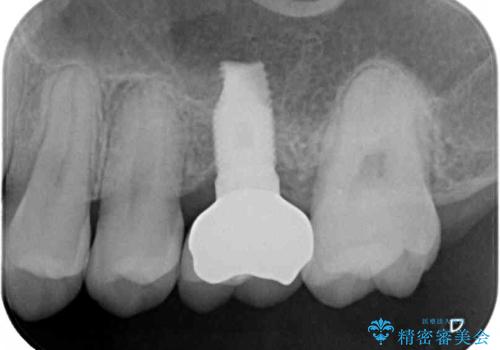

奥歯の虫歯は抜歯が必要であったので、矯正治療前に抜歯をし、矯正治療と並行してインプラントによる補綴治療を行うこととしました。

当院の特徴は、矯正治療とインプラント補綴治療の担当医が同じ歯科医師であるため、両方の治療を並行して行うことができます。